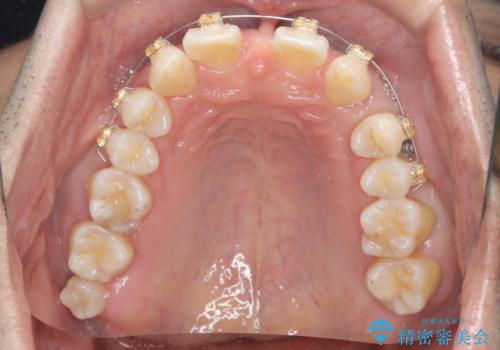

- 前歯部のすきっぱと歯並びが気になるので診て欲しいといらっしゃった方の症例です。

全顎矯正は御希望されなかったため、上顎前歯部のみの部分矯正とオールセラミッククラウンによる補綴を行いました。

- オールセラミッククラウン…¥100,000×6、仮歯…¥10,000×6、部分矯正…¥200,000費用は治療当時の料金となります

今回用いたオールセラミッククラウンはジルコニアフレームという白い素材の上にセラミックを盛っているため、審美性が非常に高いのが特徴です。

また、ジルコニアは人工ダイヤモンドの材料にも使われているほど高い強度を持っており、そのためオールセラミッククラウンは審美性だけでなく、奥歯やブリッジの補綴も可能とするクラウンです。